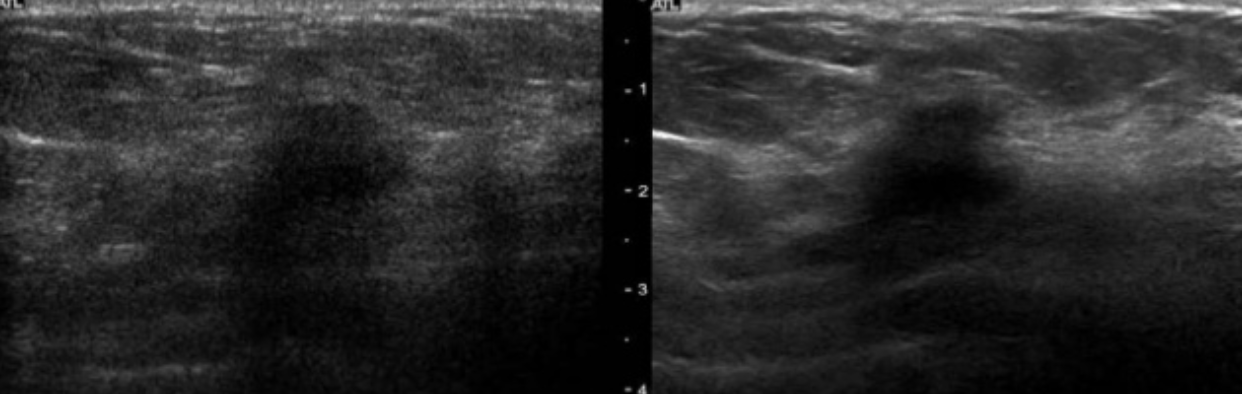

Name the artifact in the image on the left (improved appearance on the right)

What is the cause of the artifact? How can you fix it?

Speckle: interference of echoes from the distribution of scatter in tissue, causing a granular appearance of the image

FIX: increase frequency, spatial compounding, THI